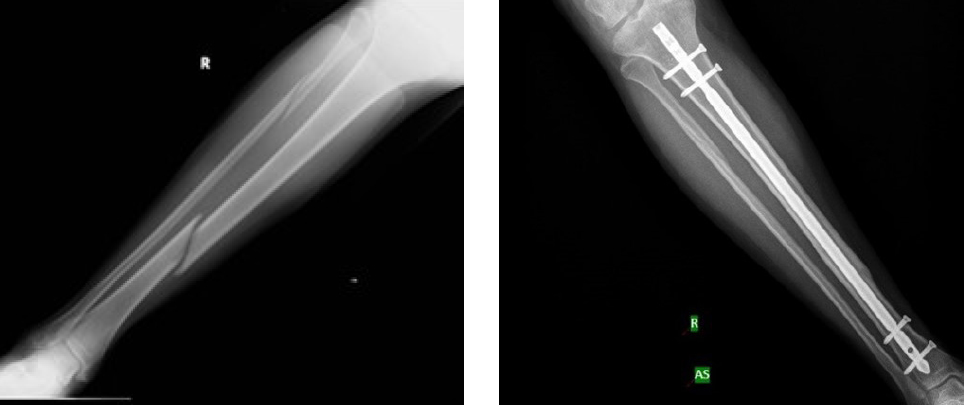

On examination, he was found to have diffuse swelling and tenderness over the shin and significant compromise in mobility suggestive of right tibia/fibula fracture. He was also noted to have chronic swelling and decreased mobility of bilateral knee joints suggestive of chronic synovitis. His right lower limb was immobilised with a slab and his leg was closely monitored for any sign of compartment syndrome. X-ray of the right leg (AP/lateral view) showed a closed tibia-fibula (transverse) shaft fracture (Figure.1).

Figure 1.

X-rays of right leg (A/P) lateral view, showing closed tibia-fibula (transverse) shaft fracture (left) and interlocking nail post-surgery (right)